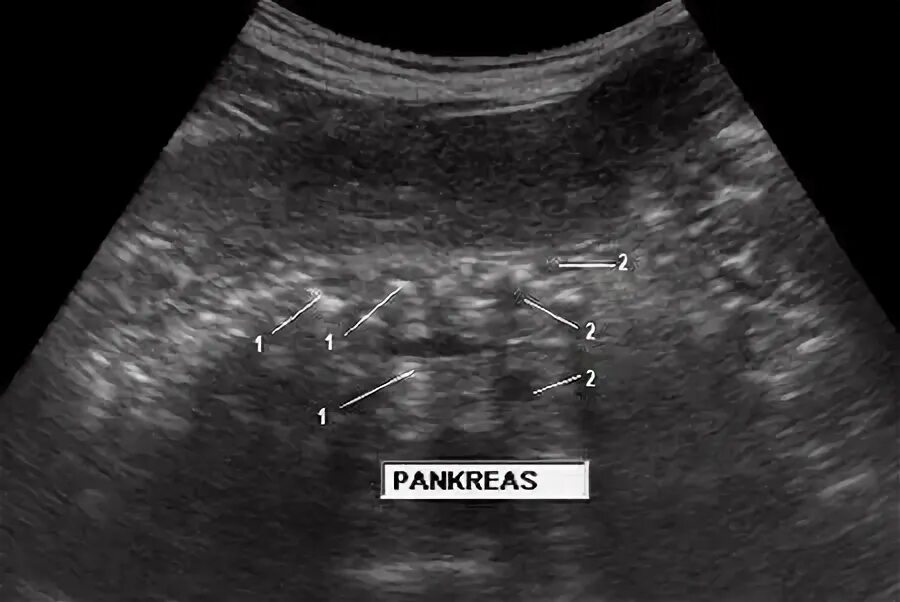

Повышенной эхогенности неоднородной структуры